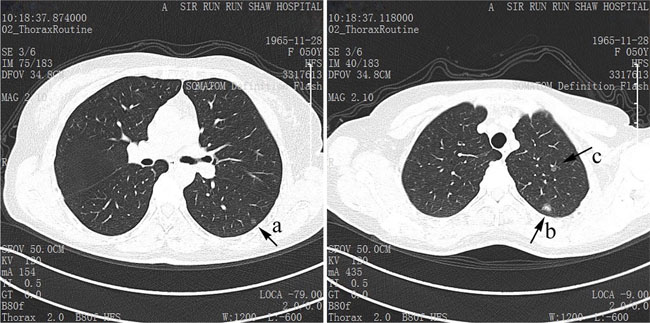

The surgery information is shown in Table 2. In cases of AIS, 70.1% underwent wedge resection, 14.3% segmentectomy, 15.6% lobectomy; while in cases of MIA, 67.0% underwent wedge resection, 23.4% segmentectomy, 9.6% lobectomy. There was difference in the distribution of location. In AIS, 30.3% nodules were located in right upper lobe (RUL), 9.0% in right middle lobe (RML), 13.5% in right lower lobe (RLL), 30.3% in left upper lobe (LUL), and 16.9% in left lower lobe (LLL). In MIA, 36.5%, 8.3%, 17.8%, 23.7%, 13.7% were respectively located in each lobe. We observed the tumor size of 35 cases (45.5%) of AIS and 103 cases (52.3%) of MIA larger than 0.8 cm. 8 (10.4%) of AIS were multiple nodules while 35 (17.8%) of MIA. Lymph node sampling was done in 38 AIS cases and 115 MIA cases, ranging from one node to 61 lymph nodes, resulting in none lymph node metastasis. The typical images of AIS or MIA in the chest CT are shown in Figure 1.

Figure 1: The typical CT images of AIS and MIA. The nodule a and c are typical AIS, and the larger nodule b in the left upper lobe is MIA.